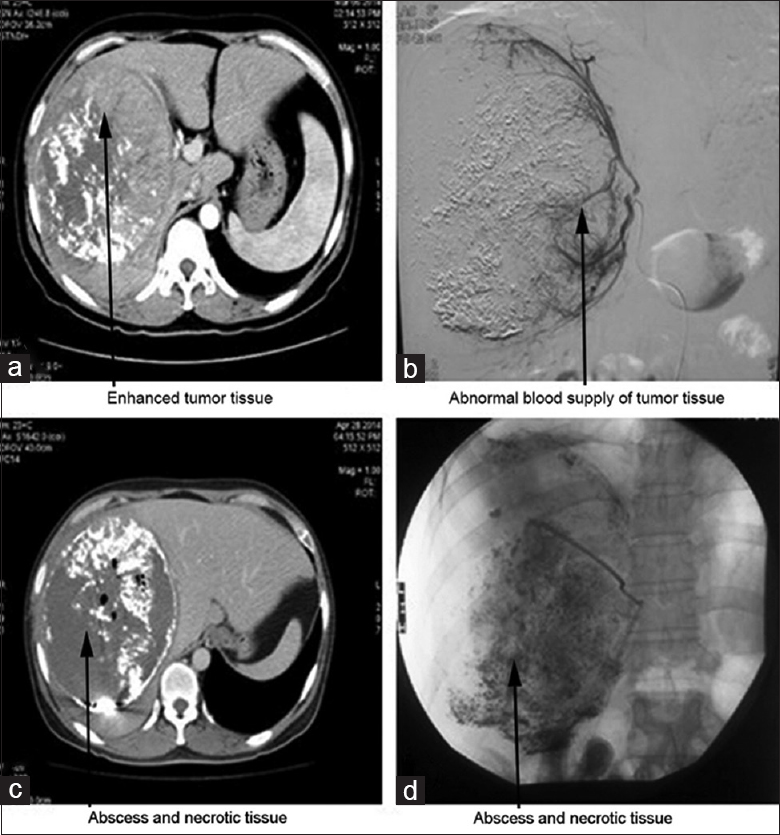

Abscessos malignos ocorrem em tumores primários (hepatocarcinoma), tanto por necrose no centro do tumor quanto por obstrução das vias biliares, quanto secundários (metástases), sendo mais raras nesses. Mas os abscessos malignos mais comuns são os relacionados ao tratamento desses tumores.

Imagens de um homem de 41 anos com hepatocarcinoma primário evoluindo com abscesso após quimioembolização transarterial. (a) imagem após primeira QE; (b) imagem após segunda sessão; (c) imagem após a segunda sessão mostrando abscesso; (d) imagem após drenagem percutânea do abscesso (fonte)

Tanto os tumores primários quanto metástases podem ser tratados por quimioembolização transarterial (TACE) ou ablação por radiofrequência (RFA). Ambos os métodos produzem necrose (morte) do tumor e da região ao seu redor, deixando um tecido que pode se infectar. O risco é muito baixo, não havendo no momento indicação clara de antibioticoterapia profilática nesses procedimentos, mas como eles se tornaram mais frequentes a sua participação nos casos de abscesso está aumentando.